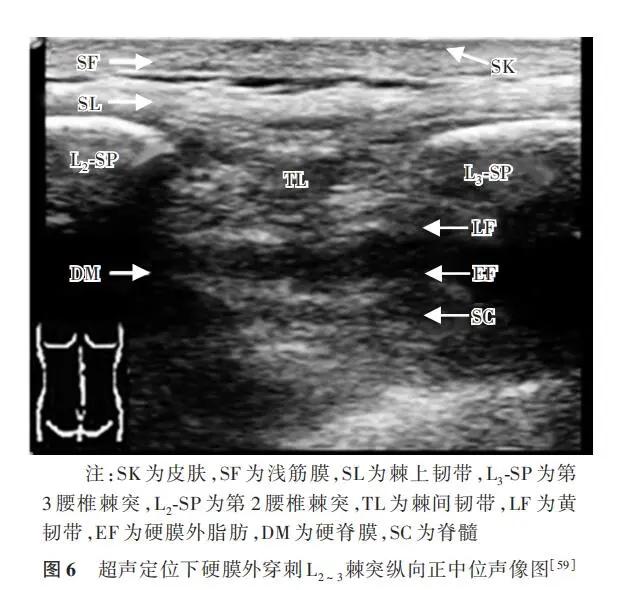

超声声像图表现(由浅到深)最浅层为皮肤,筋膜呈线状强回声,相邻棘突呈“城墙样”,骨表面为弧形线状强回声,后方被声影遮盖。在两棘突顶端由于各组韧带纤维走向不同,超声声束产生各向异性,棘上韧带、棘间韧带和弓间韧带为中等偏低不均匀回声声像。硬脊膜和黄韧带组织结构致密,声像图内显示为中等偏强回声带,以黄韧带为主,在硬脊膜与黄韧带之间为硬膜外腔,腔内可见中等偏低回声的硬膜外脂肪声像(图6)。操作者根据采集到的椎间隙影像,将硬膜外穿刺针穿过黄韧带进入硬膜外间隙。当穿刺针抵达黄韧带时阻力增大,将穿刺针芯退出,接上低阻力注射器,缓慢注入含有气泡的生理盐水;当穿刺针突破黄韧带后,回抽无脑脊液和血液,气泡无压缩,生理盐水推注无阻力,即确认穿刺成功。